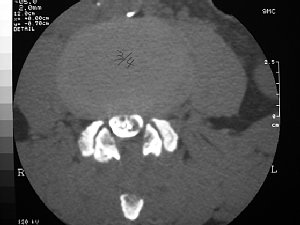

難病の頚椎後縦靱帯骨化症の手術前 |

手術後 | ||